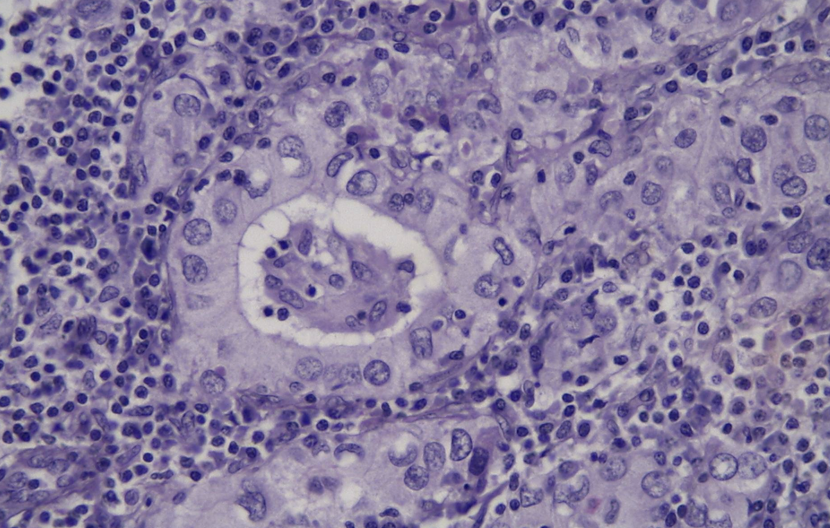

ductaal carcinoma in situ: wat is het

vroege stage van kwaadaardige borstkanker

pathologische kenmerken ductaal carcinoma in situ

verstoring architectuur klierbuizen

kleine klierbuizen: gevuld met tumorcellen

grote klierbuizen: centrale necrose

anisocytose, anisonucleose & mitose

basaal membraan intact (niet-invasieve tumor)

inflammatoir infiltraat mogelijk